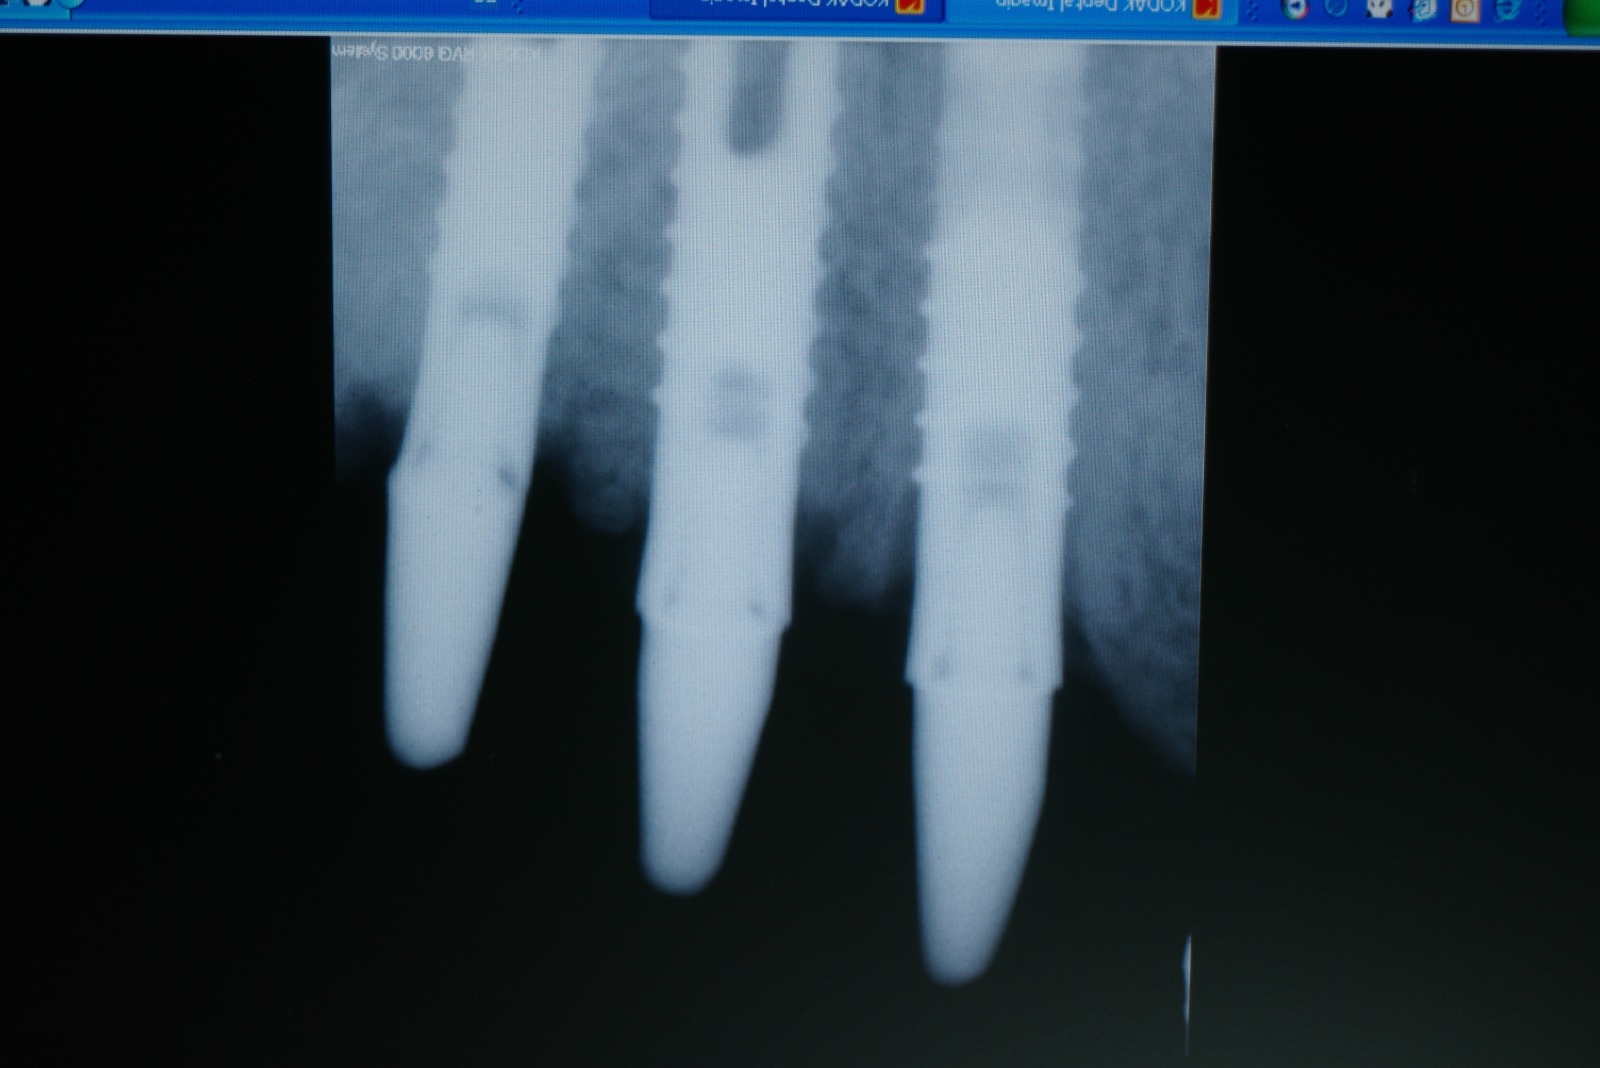

El paciente no presenta incidencias hasta el año 2005, cuando acude a consulta con el segmento distal derecho desprendido y en el que se había producido una fractura de los aditamentos macizos a nivel de la unión del aditamento con implante, de forma que la rosca fracturada del aditamento está encajada dentro de los implantes.

El tratamiento que se intento fue extraer las roscas rotas con ultrasonidos, pero no se pudo, por lo que procedimos a realizar el vaciado de estas roscas rotas y a realizar unas espiras nuevas en estos vaciados con un set de machos roscantes, para después roscar nuevos aditamentos originales de la casa ya fabricados en aleación de titanio (grado V) . Una vez instalados los aditamentos procedimos a su tallado y a realizar la prótesis ceramo–metálica como tenía antiguamente.